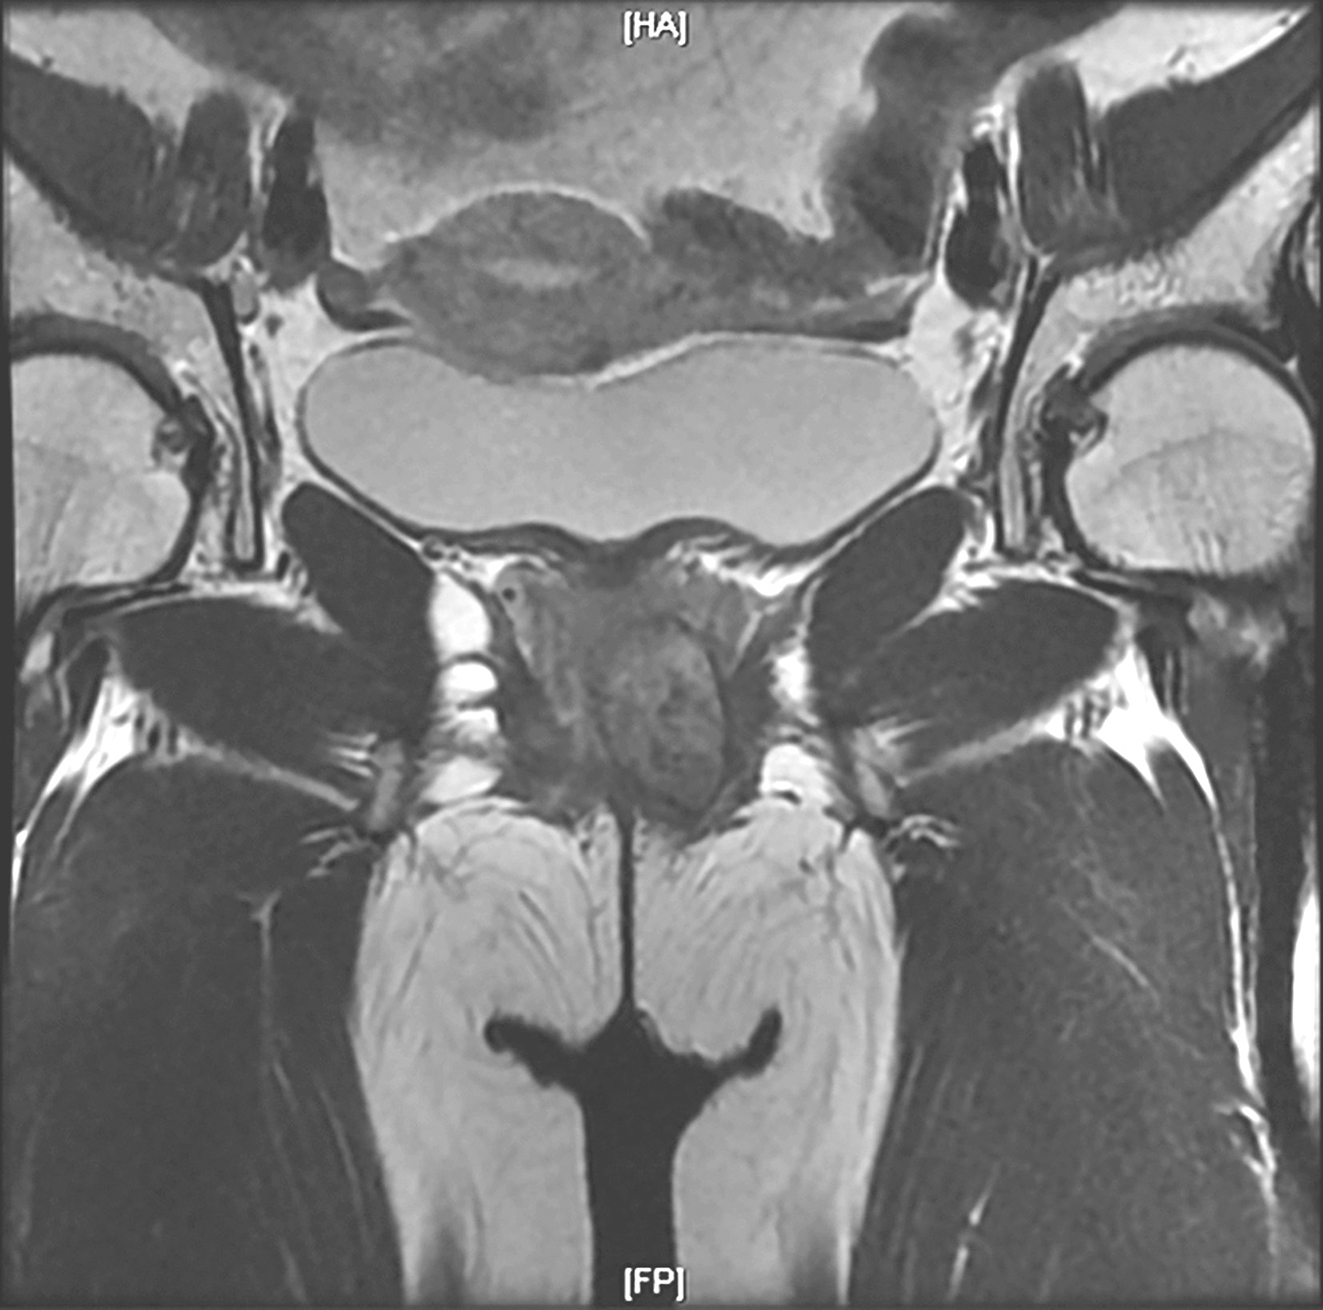

盆腔MRI(图5):直肠下段与阴道间GIST,与阴道后壁及直肠前壁分界不清,大小约为3.3cm×2.1cm×1.7cm,与前片比较无显著变化,DWI未见明显高信号,增强扫描未见明显强化。盆腔存在少量积液。

A

B

图5 术前盆腔MRI表现